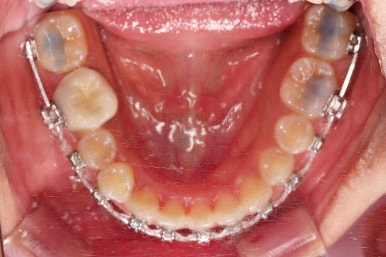

문제의 시작은 바로 아래 앞니였어요.

맨 아래 오른쪽 사진에 화살표를 보시면 앞니가 4개여야 하는데 3개 밖에 없네요.

아래 앞니 3개인 채로 마무리를 하기도 하고 4개처럼 보이게끔 마무리를 하기도 합니다.

이번 환자분의 경우는 치아 크기와 비율, 교합 등을 전반적으로 고려해서 아래 앞니가 마치 4개인 것처럼 마무리를 하기로 했습니다.

뒤쪽 치아를 차례차례 끌고 당겨와서 앞니를 대신하는거죠.

이제는 아래 앞니가 3개이기 때문에 생기는 중앙선의 문제, 치아 갯수의 문제를 맞춰나가기로 했습니다.

계획은 오른쪽 아래 송곳니 ~ 어금니 모든 치열을 앞쪽으로 밀어줘 아래 앞니를 마치 4개인 것처럼 만드는 것입니다.